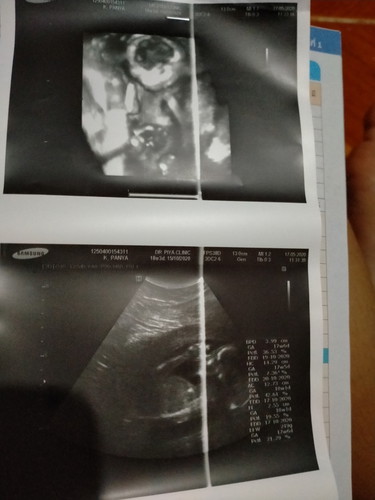

21w4d

บ้านนี้20+5กำหนดคลอด25ตุลาคมหมอบอกได้ลูกชายจ้า😊

บ้านนี้20+3จ้า กำหนดคลอด24ตุลาจ้า ลูกชายจ้า